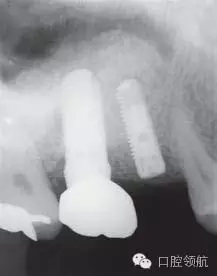

圖1 術(shù)前牙片。由于上頜竇底黏膜提升植骨術(shù)而在上頜竇內(nèi)生成的骨已完全消失。

圖8 術(shù)后8個月的牙片。兩顆種植體愈合良好。

圖9 術(shù)后8個月戴入上部修復(fù)后的曲面斷層片。